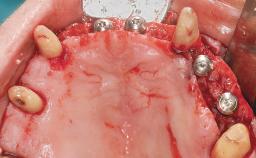

Conventional Loading of Eight Implants in the Maxilla and Final Restoration with a Full-Arch Gold-Ceramic FDP

# of Implants 8

Type of Implants One-Piece

Defining Characteristics Fully edentulous upper jaw to be rehabilitated with four or more implants